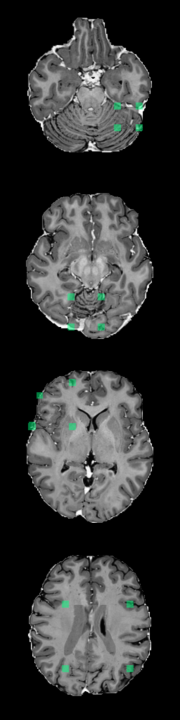

Using the synthetic test data described in Section 3.1, we evaluate the method’s ability to detect different types of outliers. Figure 3 displays the model’s response to a sink/source deformation outlier and a normal sample. The plot includes abnormality scores for individual slices across the entire volume. Slices that include the artificially deformed sphere produce a strong and consistent activation (Figure 3, red). Meanwhile, normal slices elicit only weak activations (Figure 3, blue).

In addition to the synthetic test set, which only includes local abnormalities, we provide examples of global abnormalities in Figure 5. A normal sample produces minimal activation in its canonical orientation (Figure 5, left most image in (a)). However, rotating the sample produces scattered activations throughout the entire volume (Figure 5, (a)). Blurring or substituting different anatomy produces even stronger activations (Figure 5, (b)).